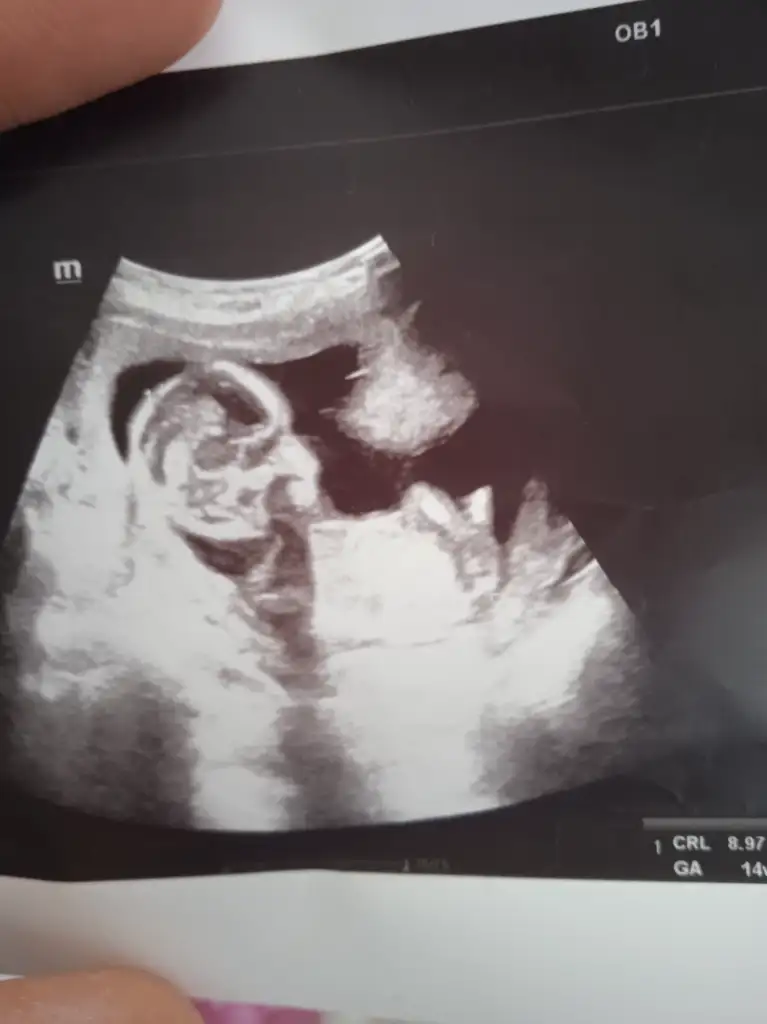

erkekBana da bakar mısınız. Doktor tahminde bulunayım dedi ama parti istediğimiz için söyletmedik. 11. Hafta